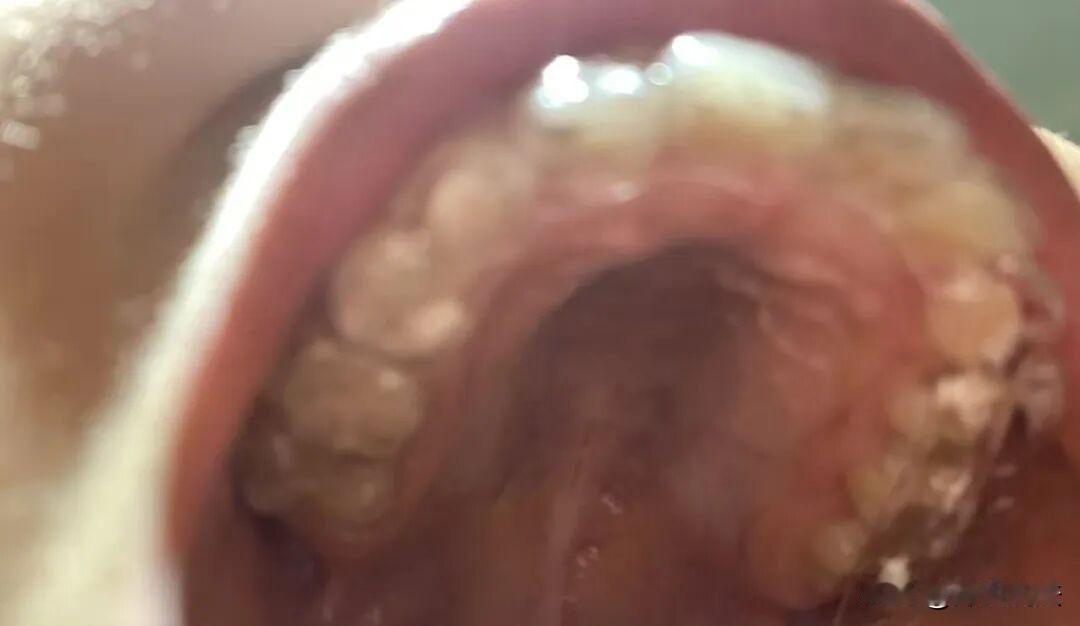

福建福州,男子在一家知名专业门店给女儿矫正牙齿,哪知在两年后女儿出现了一系列的健康问题,比如牙龈出血红肿等情况。男子去向店方求助的时候,惊讶的发现这家店所提供的牙套竟然是无证生产,最终该男子走上了维权的道路。 据极目新闻报道,2020年10月的时候,蒋先生的女儿在蒋先生的支持下,选择了在福州市某店做牙齿矫正服务。 据蒋先生透露,这次牙齿矫正,一共支付了25800元。 蒋先生表示,为了自己的女儿,他愿意付这么高的牙齿矫正服务费。 让人没有想到的是,在2023年的时候,蒋先生的女儿出现了一系列的口腔问题,比如牙龈出血红肿等。 对此蒋先生有些郁闷,于是便再次找到了那家店的负责人,但负责人的处理态度让蒋先生对其服务产生了怀疑。 对方表示,要蒋先生自行把他女儿的牙套处理一下,然后再给孩子带上。 这样的处理态度让蒋先生立马想起第一次给女儿装牙套的事情。 那天,他拿出店里给他的牙套,却惊讶的发现,这个牙套既没有产品外包装,也没有品牌标识。 这让蒋先生有些不安,随即他便直接再次找到了该店的负责人,要他们提供自己女儿佩戴牙套的产品合格证,然而却被拒绝了。 对方表示这种信息属于商业机密,是很难查到的。 但是蒋先生并没有死心,他又向市监局所报,这次举报后,市监局给蒋先生提供了一份这家店所出售牙套的供应商的信息。 蒋先生在拿到这些信息后,再度进行调查,结果却发现这些信息都是假的。 在蒋先生的施压下,该店的负责人又改口了,这次他们宣称蒋先生女儿佩戴的牙套系另一家专业公司的产品。 但是让人没有没有想到的是,在蒋先生的调查下,才发现这家门店的牙套产品属于无证生产的产品,并且它的客户量相当之多,足有450名之多,最终蒋先生直接把该店起诉了,要求其承担相关法律责任。 那么从法律角度,该如何看待蒋先生所发生的这件事呢? 根据《产品质量法》第27条:产品或者其包装上的标识必须真实,且要有中文标明的产品名称、生产厂厂名和厂址。 本案中,蒋先生在收到该店的产品后,发现它没有生产证书。根据上文法律规定,这种商品属于非法商品,因此该店的行为涉嫌销售三无产品的违法行为。 那么,该店会受到什么惩处呢? 根据《消费者权益保护法》第五十五条规定:经营者提供商品或服务有欺诈行为的,应按消费者要求增加赔偿损失,赔偿金额为商品价款或服务费用的三倍;增加赔偿金额不足五百元的,为五百元。 在本案中,该店售卖的牙套是没有生产资质的牙套,但是他们两三无产品当成大品牌高价卖给蒋先生,这种行为属于商业欺诈。 蒋先生可以根据法律规定,要求该店按照法律规定退一赔三。 同时,因为销售三无产品属于违法行为,根据相关的行政处罚规定,该店还会受到相应行政处罚,且不得继续销售这种牙套。 经审理认为,该店构成消费欺诈,判该店返还蒋先生支付的医疗费25800元,并三倍赔偿77400元。 对于本案,你怎么看?